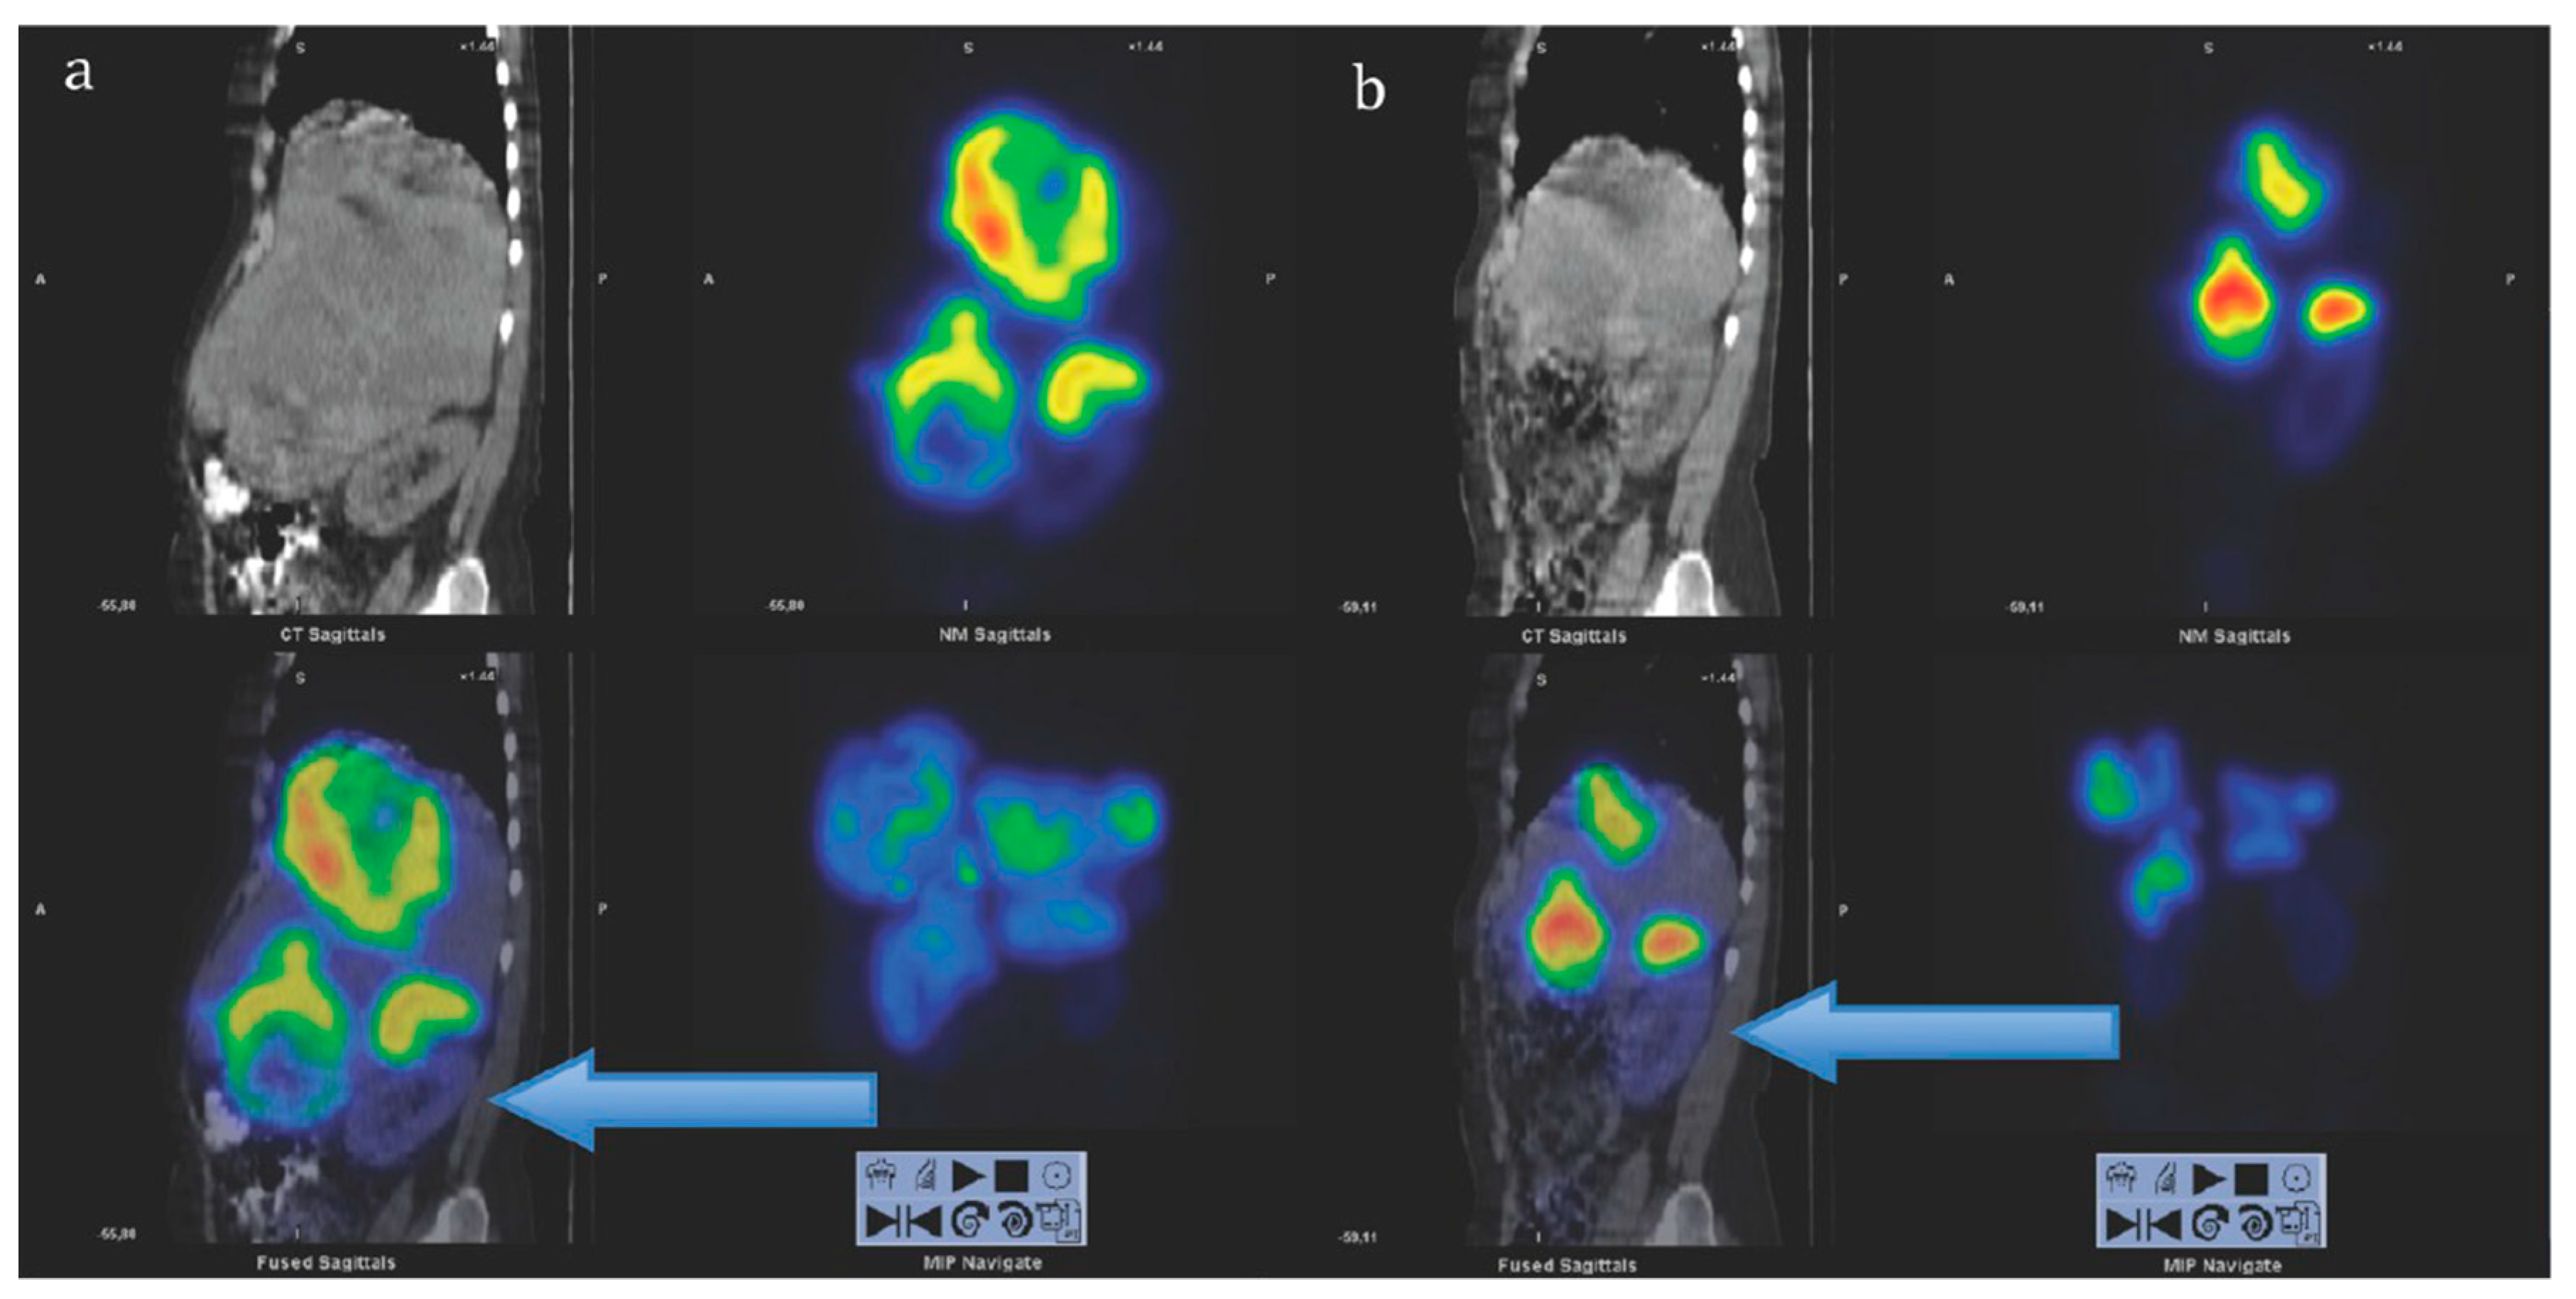

Figure 6.

Sagittal views of single photon emission computed tomography (SPECT)-CT over the abdomen at the level of the right kidney, 24 hrs after infusion of 7.4 GBq of [177Lu]Lu-DOTA-octreotate. (a) Cycle 1, May 2010 (b) cycle 7, August 2011. Left upper corner in each image: Attenuation correction CT, right upper corner attenuation corrected SPECT, left lower corner fused SPECT-CT, right lower corner maximum intensity projection (MIP). Note the position of the right kidney (arrow) and tracer distribution within the tumors. Reproduced from [116].